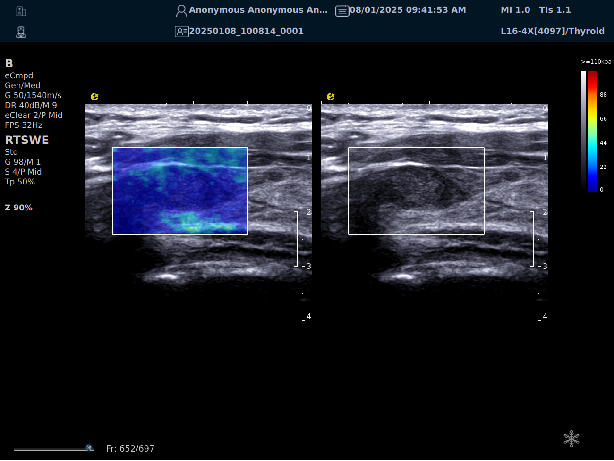

实时剪切波弹性成像

评估组织的软硬,并且提供定量数值,从而提示组织的良恶性。

鉴别诊断、精准分级、定量评价、穿刺引导、疗效评估、随访观察

恶性占位常常向周边组织进行侵润及扩散,二维很难观察到浸润部分的边界。使用实时剪切波成像能够对占位及周边组织进行硬度评估,通过颜色编码来区分不同组织的硬度信息,直观的观察占位组织的边界信息,更方便区分占位组织和正常组织的边界,准确评估消融范围。